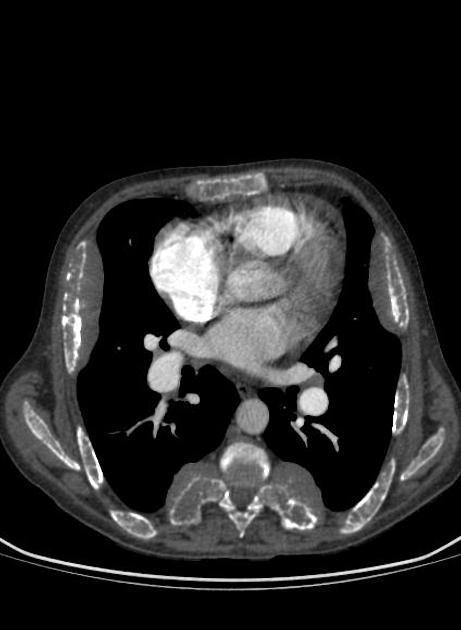

HOMEM DE 20 ANOS COM QUADRO DE INSUFICIENCIA RESPIRATÓRIA E HEMOPTISE. NEGA FEBRE

OPACIDADES DIFUSAMENTE DISTRIBUÍDAS, COM PADRÃO SUGESTIVO DE PREENCHIMENTO ALVEOLAR, PREDOMINANTE EM LOBO INFERIOR DIREITO

HEMORRAGIA ALVEOLAR